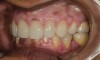

A 40-year-old female patient complained of short teeth and asked for various options to improve her smile. On clinical examination, the palatal surfaces of the maxillary anterior teeth were found to be eroded, with the residual tooth structure having a smooth and shiny appearance (Figure 1 through Figure 3). In MIP, no restorative space was available, as the lower anterior teeth fit tightly into the upper palatal surfaces, making this a clinically challenging situation to treat conservatively. In most cases of conventional treatment protocols, such upper teeth are devitalized and restored with crowns that structurally leave the teeth in a compromised condition.10

Fig 3. Preoperative view showing erosion of palatal surfaces of upper anteriors.

Figure 3